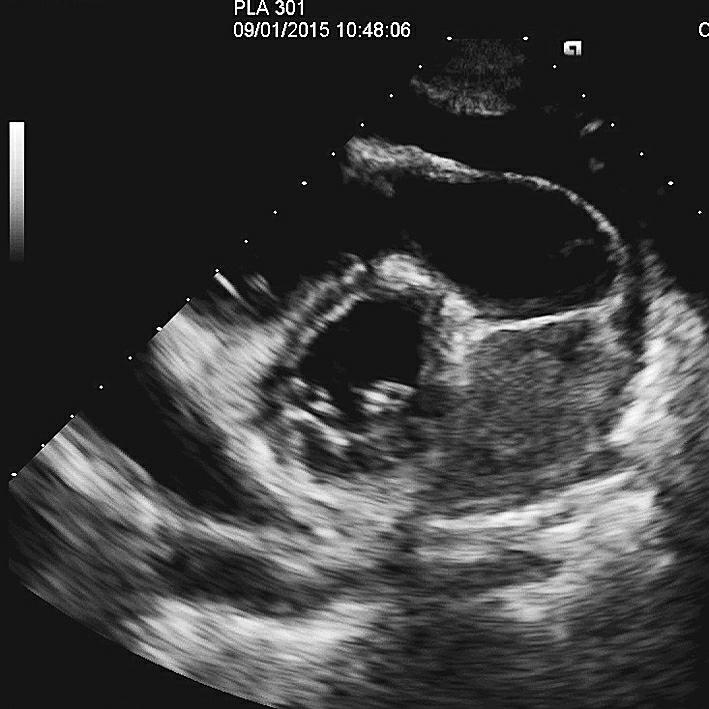

病理结果(2015年9月6日):经超声引导下取出的3条组织,镜下见肿瘤细胞呈乳头状及腺样结构排列并浸润横纹肌,瘤细胞小圆形,大小较一致,免疫组织化学结果显示肿瘤具有双向分化特点,符合恶性间皮瘤(图5)。免疫组织化学染色结果:波形蛋白(vimentin)(+),CK5(−),钙视网膜蛋白(calretinin)(−),Ki-67(+20%),WT-1(个别细胞+),CK(+),D2-40(+)(图5B)。经口服多维元素片1周后,转入肿瘤科接受进一步化疗,方案为培美曲塞二钠1g+顺铂60mg i.v.gtt. D1,同时心包腔内注射顺铂60mg。

图5病理图像-7646139261093888

图5病理图像-7646130214520832

图5病理图像

A.镜下见肿瘤细胞呈乳头状及腺样结构排列并浸润横纹肌;B.免疫组化结果显示肿瘤具有双向分化特点,符合恶性间皮瘤